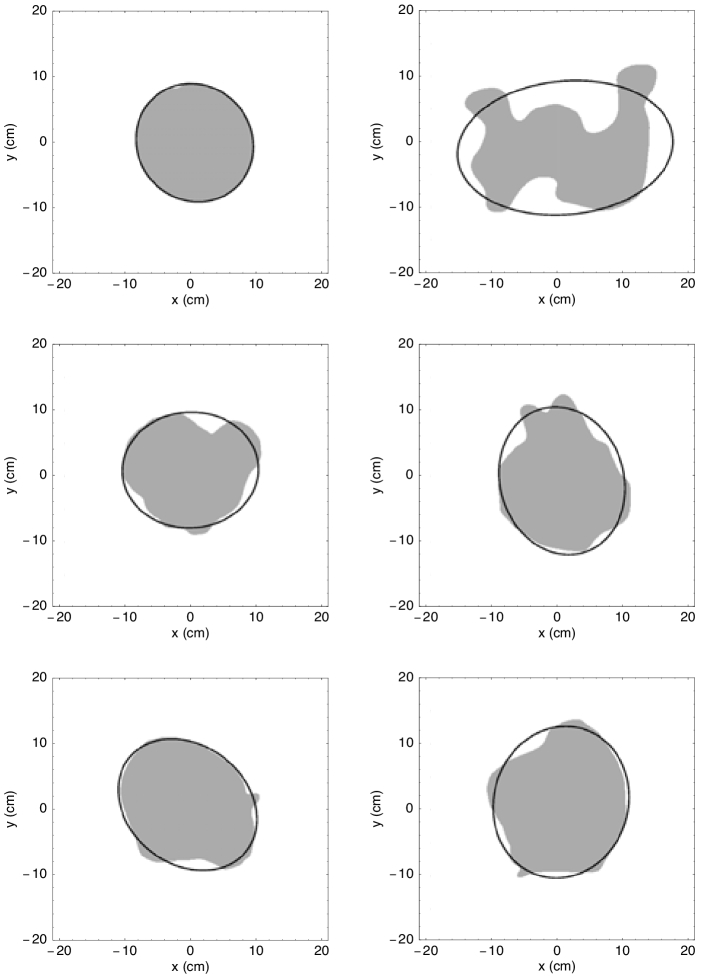

3.1 Interpolation of Chorionic Plate Outlines

Figure 1 shows typical fits to the data points of chorionic plate outlines obtained with the method described in A. Two types of outlines are shown: one with a single-valued and one with a multi-valued radius. A single-valued radius means that a line emanating from the centroid intersects every point on the perimeter only once, while a multi-valued radius function may intersect the perimeter more than once. In the latter case, the perimeter folds back on itself, and the corresponding chorionic plate has lobes or some other irregular shape. Note the irregular spacing of the points along the perimeter, as described in Sec. 2.1. The outline with the single-valued radius has a regular shape, so relatively few data points are needed. However, the outline with the multi-valued radius has intervals where more points are needed to describe regions of greater curvature, which can occur for a small protrusion or, as in this case, a large morphological entity such as a lobe. This is reflected in the number of terms that must be included in the Fourier series to produce an accurate interpolation. The series for the outline with the single-valued radius required fewer terms than that for the outline with the multi-valued radius because regions of larger curvature mean that more rapidly varying trigonometric functions must be included in the interpolation.

The moment expansion method described in B has been used to calculate the best-fit ellipse for the chorionic plate of each placenta in the cohort. This includes the semi-major and semi-minor axes and the orientation angle. Figure 5 shows a selection of placentas together with their best-fit ellipses. Most apparent from this figure is that some outlines fit their ellipse quite well. These correspond to chorionic plates with regular shapes. For chorionic plates with irregular shapes that have pronounced lobes and other protrusions, the ellipse does not provide as good a fit. As expected from the discussion in B, such placentas have appreciable higher-order moments to account for their irregularities. In such cases, quantities derived from higher-order moments, such as skewness (third-order) and kurtosis (fourth-order) provide significant additional information about placental shape. The extent to which the ellipse accounts for the shape of the chorionic plate can also be used to estimate the roughness. Any region of the chorionic outline that lies within the ellipse or crosses its boundary contributes to the roughness, as is apparent from the definition in (5).